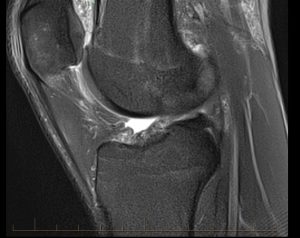

Figure 2 is a fat suppressed sagittal image of a normal knee. The patellar ligament appears as the low signal intensity structure (black) joining the inferior pole of the patellar to the tibial tubercle. The subcutaneous soft tissue anterior to this ligament is of rather uniform thickness and displays largely low to intermediate signal intensity.

FIgure 2